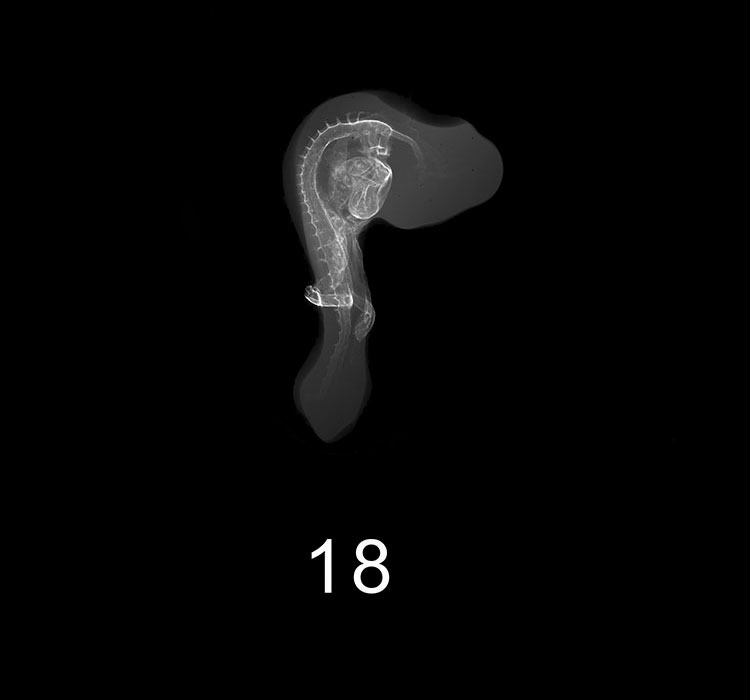

Chick Embryo Microangiography

Images listed by Hamburger-Hamilton (HH) Stage

Hamburger-Hamilton (HH) stages are a system used by those who study chick embryo development to describe the apparent maturity of the developing chick from laying of the egg to hatching. An embryo is assigned an HH stage (numbered from 1 to 46) based on its physical shape and visible features (morphology). This staging system is not dependent on the chronological age nor the size of the embryo, which are susceptible to variations due to breed, temperature during incubation, season, and time between egg laying and incubation. The stages, are in a sense, arbitrary levels of maturity based on multiple physical features. For example, embryos that might have different ages or sizes might be assigned the same HH stage based on their external appearance due to the natural variation which occurs between individuals or due to differing conditions during incubation.

The following morphological landmarks, when present, are examples of what is considered when assigning HH stages to a chick embryo: the shape and size of the primitive streak; the shape and condition of the neural tube (developing brain and nervous system); the presence and number of somites in the paraxial mesoderm; the appearance and characteristics of the branchial arches as they form the jaw, larynx and pharynx; the appearance of the limbs and the formation of wing buds, joints, and digits; the formation of eyelids, feathers and beak.